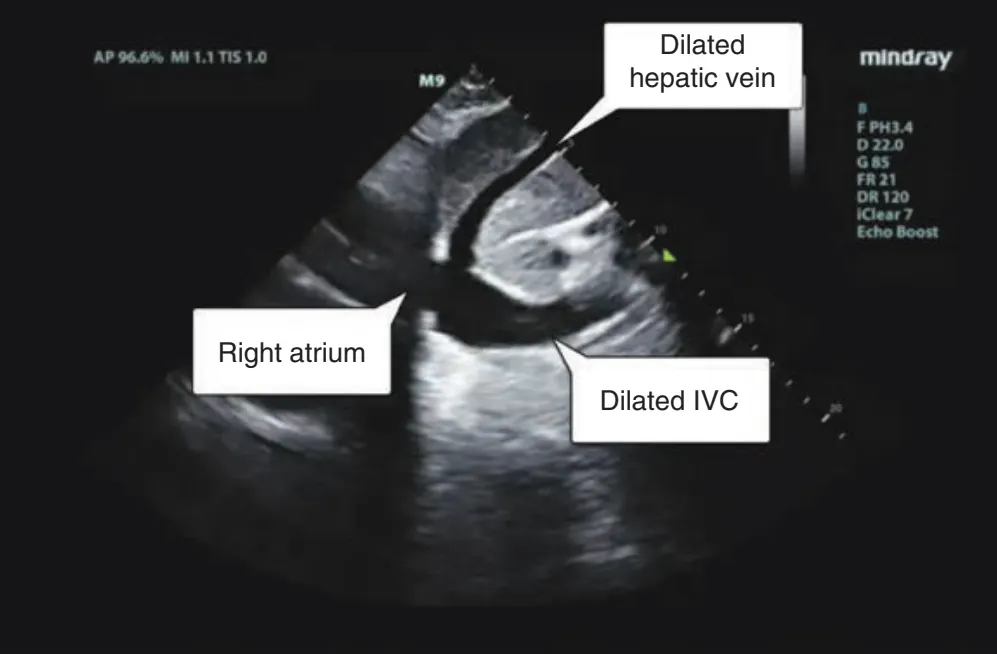

(2) Transthoracic echo : ER에서 pul. HTN을 진단하는 가장 좋은 초기검사

폐동맥 고혈압 시사 소견

: RV hypertrophy, TR, RV function 저하 (아래 그림 소견 및 TRvmax, TAPSE, IVC size 등으로 의심)

IVC와 Hepatic Vein의 확장 ⇒ RA Pressure 상승을 의미함.